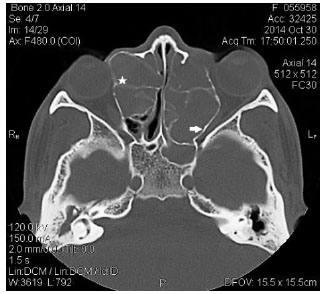

La tomografía de senos paranasales mostró imágenes de tejido blando bilateral, de apariencia homogénea, múltiple en cada lado y asimétricos, sugerentes de mucoceles. En el lado derecho los senos frontales, maxilares y principalmente el seno etmoidal anterior mostraron compresión a nivel de lámina papirácea, produciendo marcada lateralización del globo ocular. El mucocele del lado izquierdo comprometía los senos paranasales frontal y principalmente los senos etmoidal posterior y esfenoidal, ejerciendo una compresión posterior y lateral sobre el nervio óptico (Figura 3). No se evidenció compromiso intracraneal.

Figura 3 TC axial que muestra proptosis y compresión orbital anterior derecha(estrella) y posterior izquierda, con compromiso del nervio óptico(flecha).